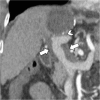

Hydatid disease is a worldwide zoonosis endemic in many countries. Liver echinococcosis accounts for 60-75% of cases and may be responsible for a wide spectrum of complications in about one third of patients. Some of these complications are potentially life-threatening and require prompt diagnosis and urgent intervention. In this article, we present our experience with common and uncommon complications of hepatic hydatid cysts which include rupture, bacterial superinfection, and mass effect-related complications. Specifically, the aim of this review is to provide key imaging features and diagnostic clues to guide the imaging diagnosis using a multimodality imaging approach, including ultrasound (US), computed tomography (CT), magnetic resonance (MR), and endoscopic retrograde cholangiopancreatography (ERCP).